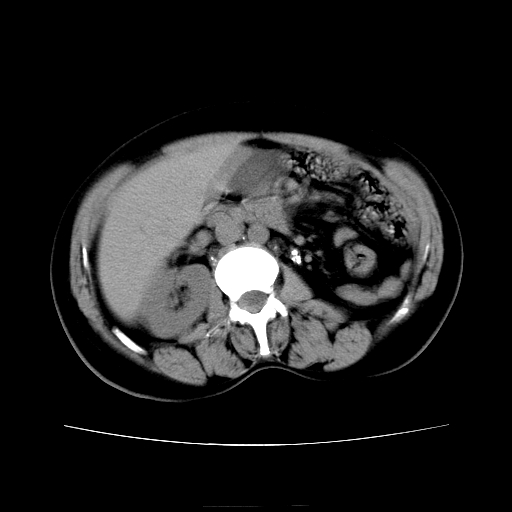

女45y多次(7次)碎石,结果不理想!曾碎石后尿出小碎石,仍腰痛,要求ct,其它不详.本人更倾向于钙化斑!无肾实质破坏,积水等提示集合系统无梗阻.另外腹腔多处钙化.是否结核后改变!谢谢赐教!

1)双肾结石。2)脾脏钙化灶。3)腹膜后多发淋巴结钙化。

尿路结石与腹部淋巴结钙化共存,建议v尿路造影检查,免得钙化灶冤枉为结石受罚。

考虑双肾结石,肾脏实质无破坏表现,没有结核病史,不考虑肾结核,